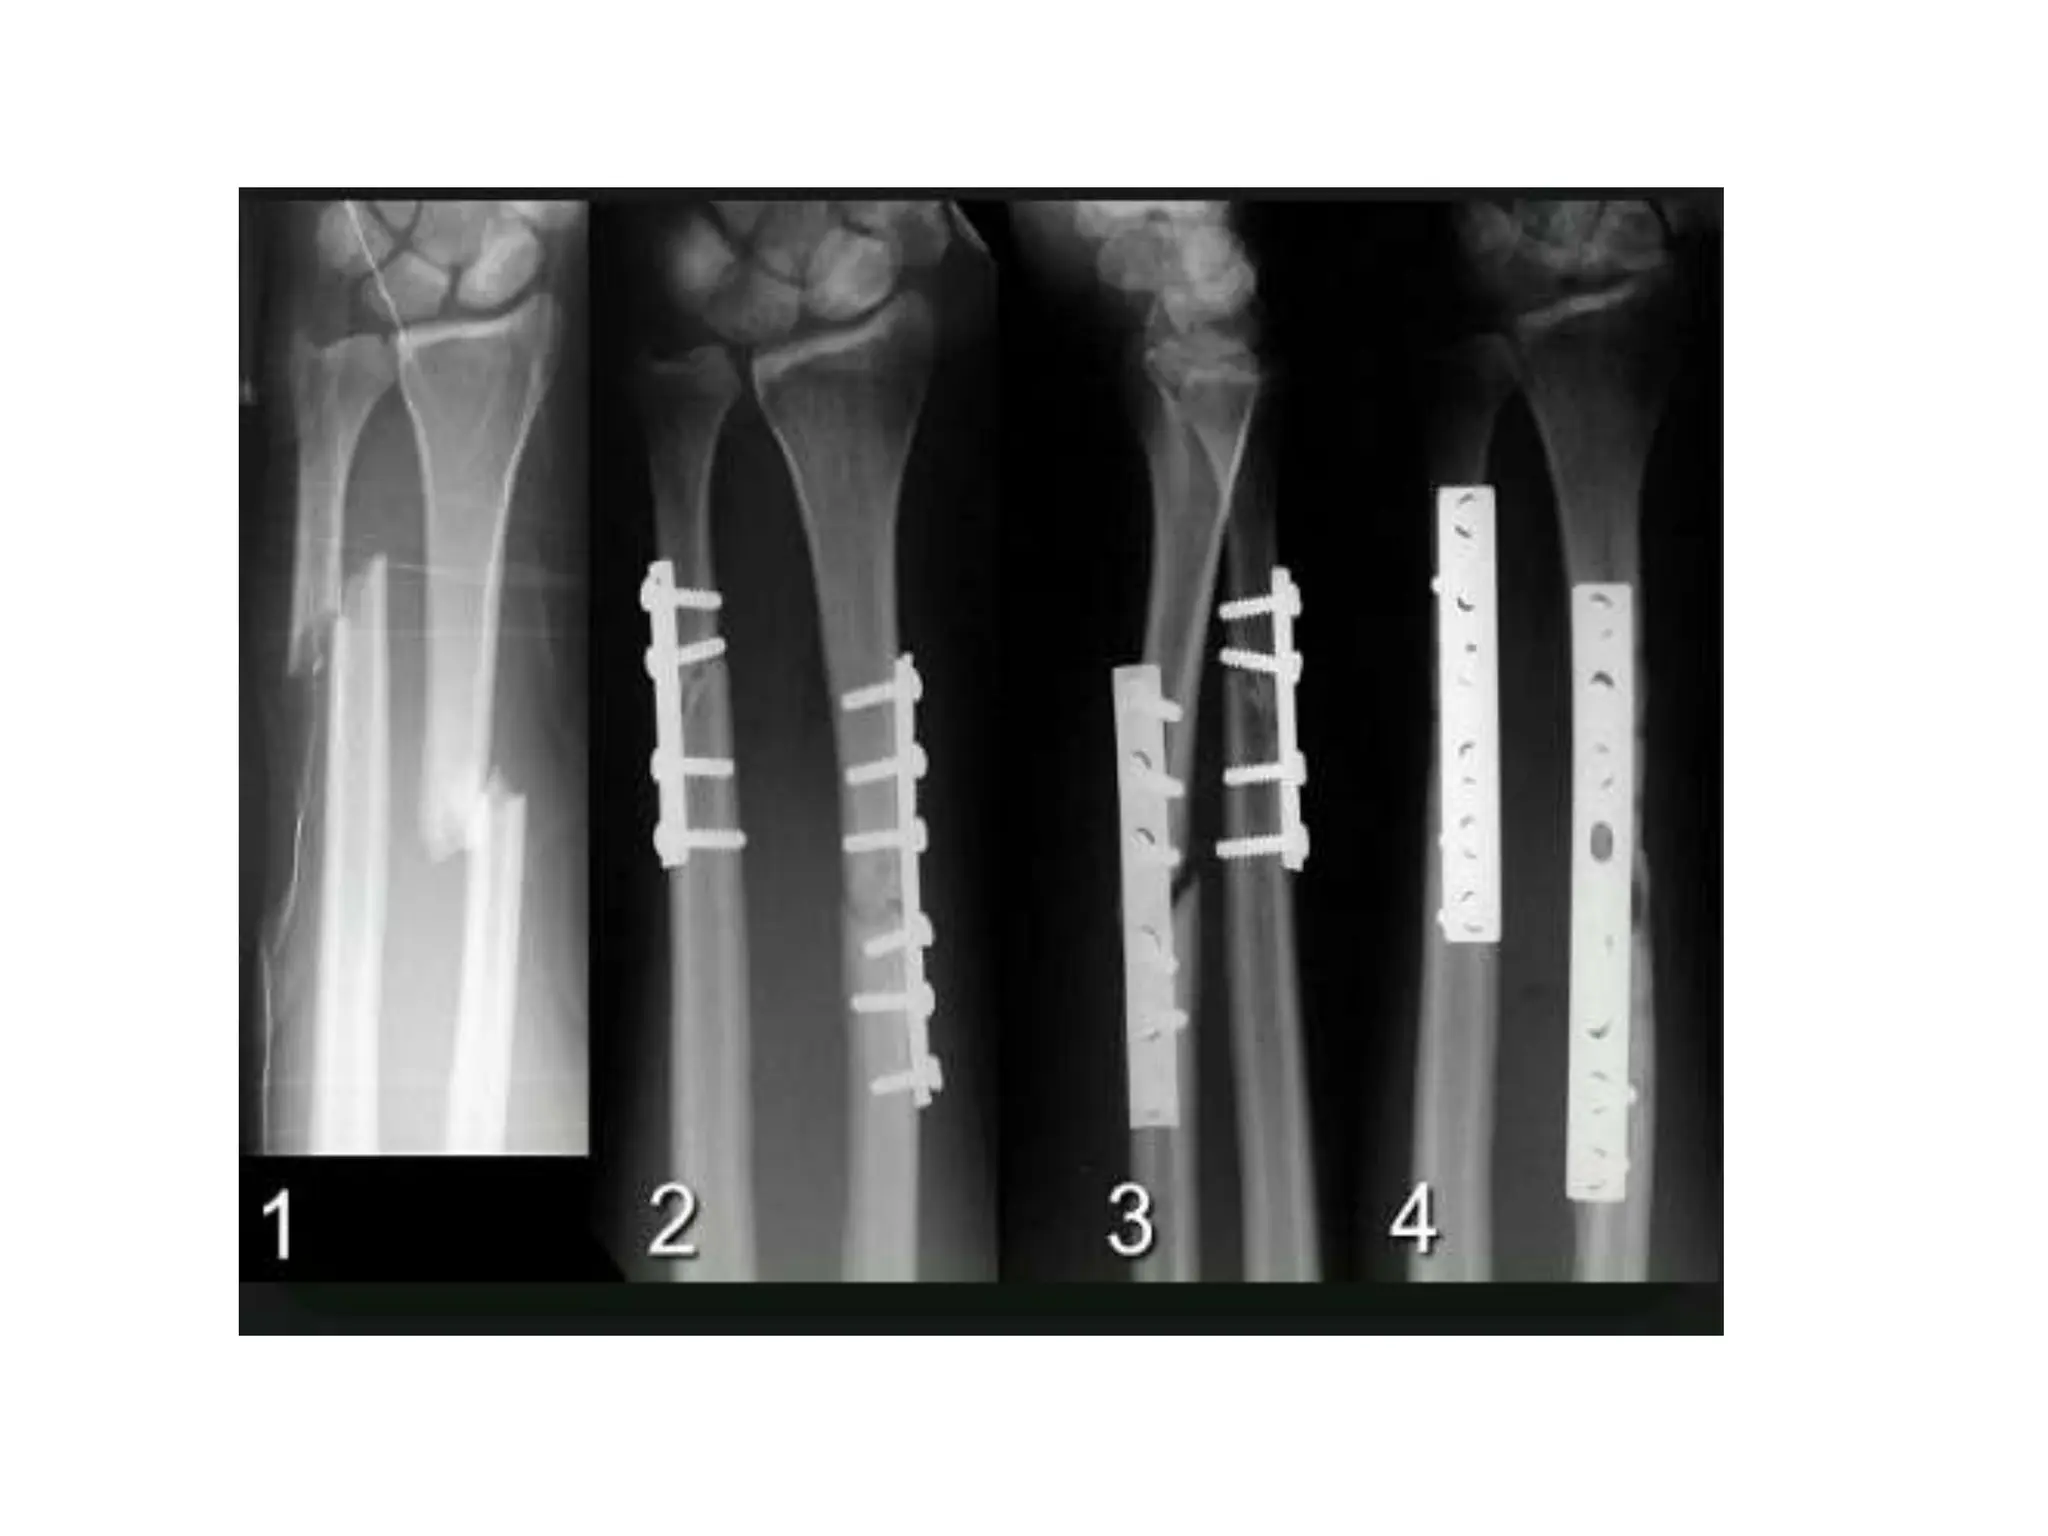

• Open reduction and internal fixation: Some

fractures , such as intra- articular fractures, are

best treated by open reduction and internal

fixation.

Plates and screw

• Useful for treating metaphyseal fracture of

long bones and diaphyseal fracture of

radius and ulna

(a)The patient was fixed with a plate and screw but did not unite (b)

external fixation was applied